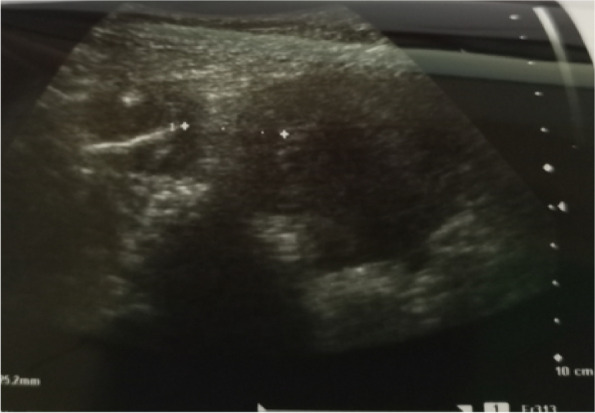

Background: Loss of Intra Uterine Device (IUD) following silent perforation of the uterus either during or after IUD insertion is an uncommon finding due to a lack of immediate follow-up. We report a rare case in which uterine perforation following the migration of IUD to the right fallopian tube without visceral injury. The patient presented with lower abdominal pain and pain during sex for one year since IUD insertion. On examination, we noted tenderness on the right suprapubic region and on speculum examination, no IUD thread was seen. A radiological pelvic examination showed an empty uterus without an IUD. Laparotomy and retrieval of migrated IUD was done followed by repair of perforated uterus.

Abstract Image